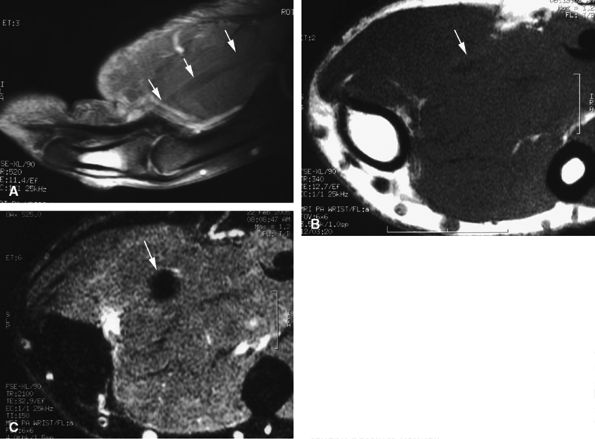

and axial MR images directly depict the tear as a thickening and a defect of the pulley (Fig. 11.55), sagittal images, which display the indirect sign of bowstringing, are more sensitive, particularly with imaging performed in forced flexion (Fig. 11.56).

FIGURE 11.55 ● Rupture of A2 pulley of the fourth finger. Sagittal (A) and axial (B) post-contrast T1-weighted images show the tear of the A2 pulley on the midline (black arrowheads) with a palmar dislocation of the flexor tendon. The pulley (white arrow and arrowhead) is now deeply located beneath the flexor tendons. Note the integrity of the A1 pulley (black arrow).

FIGURE 11.56 ● Bowstringing of the flexor tendons. Sagittal stress post-contrast T1-weighted image with forced flexion shows palmar dislocation of the flexor tendons (arrows) due to rupture of the A2 and A3 pulleys.